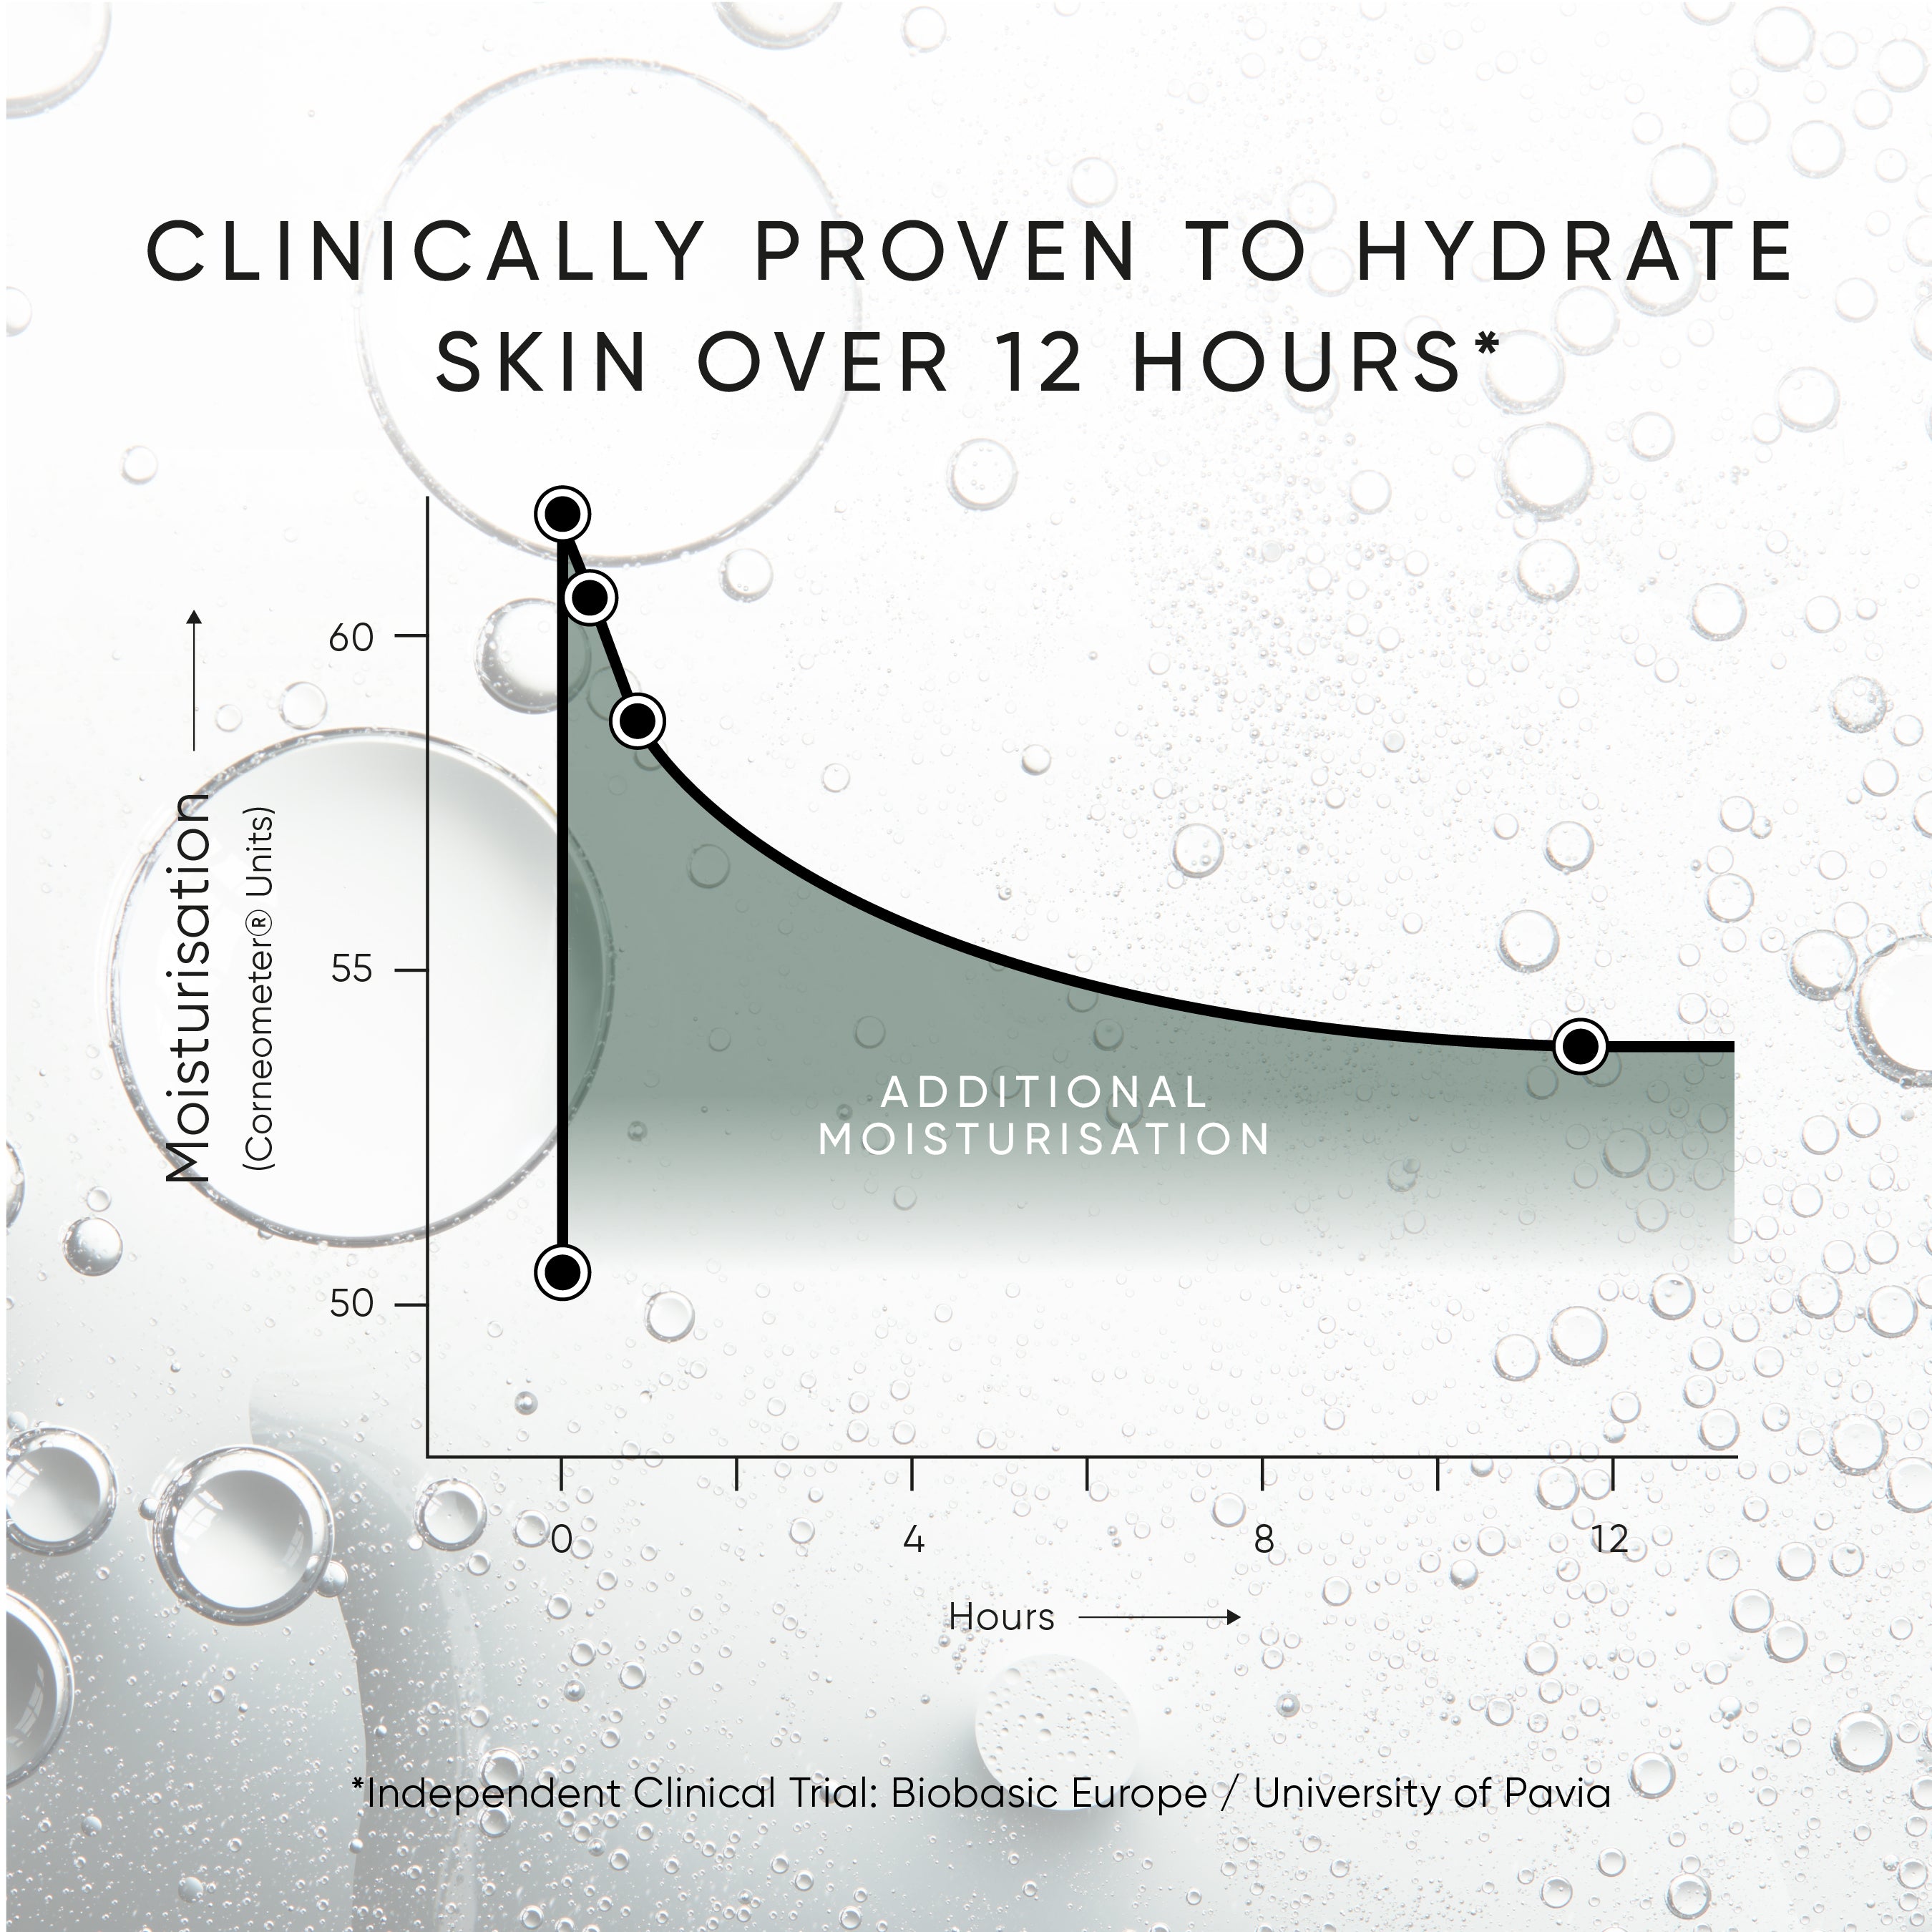

This lightweight, next-generation triple-weight Hyaluronic Acid serum is clinically proven to immediately plump the skin and provide hydration for up to 12 hours.

Clinically proven to hydrate skin over 12 hours, as well as immediately plump the skin.

This next generation Hyaluronic Acid serum is clinically proven to hydrate the skin over 12 hours. The unique triple weight blend is also proven to deliver an immediately plumping effect.

Clinically proven to hydrate the skin for over 12 hours with the triple-weight formula.